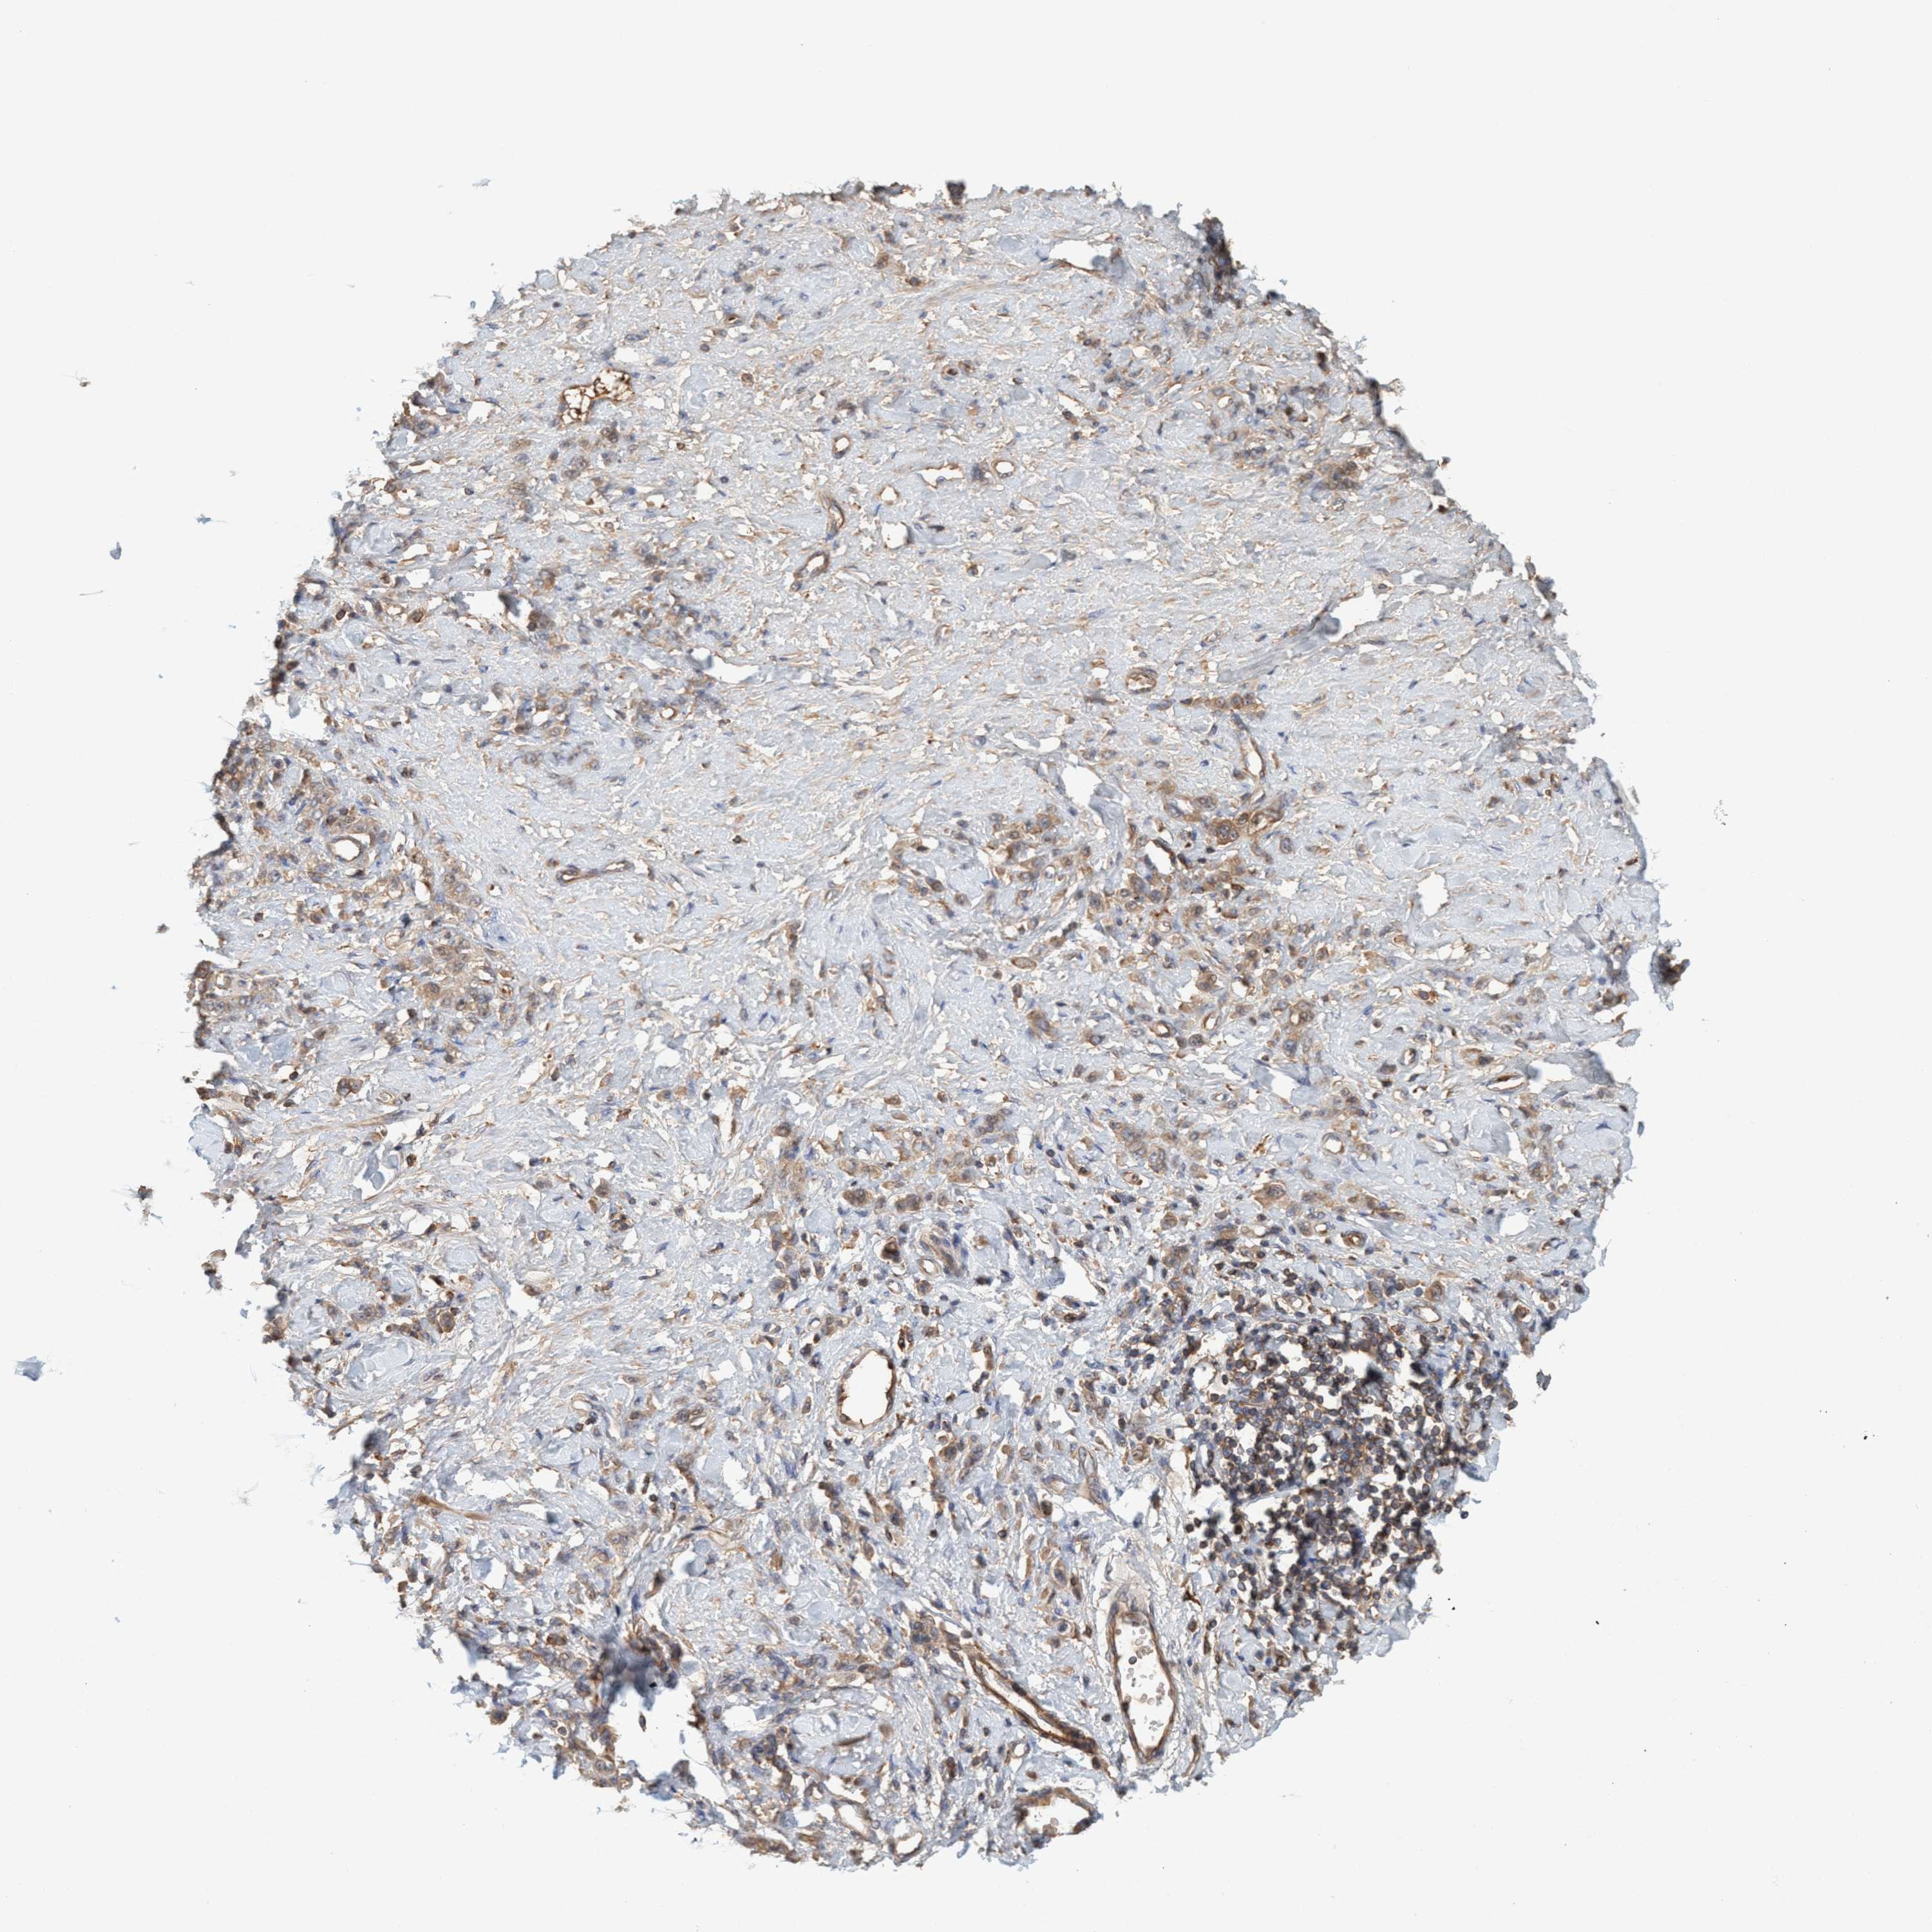

STOMACH CANCER - Protein expressioni

A mouse-over function shows sample information and annotation data. Click on an image to view it in a full screen mode. Samples can be filtered based on level of antibody staining by selecting one or several of the following categories: high, medium, low and not detected. The assay and annotation is described here.

Antibody stainingi

Antibody staining in the annotated cell types in the current human tissue is reported as not detected, low, medium, or high, based on conventional immunohistochemistry profiling in selected tissues. This score is based on the combination of the staining intensity and fraction of stained cells.

Each image is clickable and will lead to virtual microscopy that enables deeper exploration of all samples and also displays staining intensity scores, fraction scores and subcellular localization as well as patient and tissue information for each sample.

Antibody HPA021421

Antibody HPA021430

Staining

High

Medium

Low

Not detected

Intensity

Strong

Moderate

Weak

Negative

Quantity

>75%

75%-25%

<25%

None

Location

Nuclear

Cytoplasmic/membranous

Cytoplasmic/membranous,nuclear

Adenocarcinoma, NOS